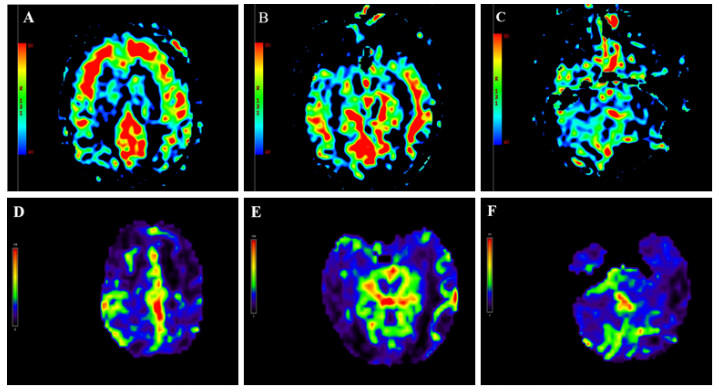

| 注:(A-C)中毒第9天,头颅ASL显示双侧额叶、颞叶皮层下白质区对称性灌注增高,双侧小脑半球灌注减低;(D-F)中毒后第6月头颅ASL显示双侧额叶、枕叶、小脑半球灌注弥漫性减低;图中红色代表高灌注,蓝色代表低灌注,黄色代表两者之间 图 2 本例患者头颅ASL灌注成像动态变化 |

患者中毒后第20天出院,并转至本地康复医院继续治疗,方案包括高压氧促进脑功能恢复、药物预防癫痫发作,辅以低频电刺激、电动起立床训练、针灸等康复治疗。康复过程中患者持续经鼻饲进食,大小便无法自控,中毒后第3个月GCS评分7分(E2V2M3)。坚持以上康复方案,中毒后第6个月,GCS评分10分(E3V3M4)。复查头颅MRI:双侧额顶枕叶皮层下可见少许斑点片状及条片状DWI稍高信号影,较前高信号减低,范围缩小,脑室系统明显扩大,皮层萎缩,见图 1I ~图 1J。磁共振ASL:双侧额顶枕叶、小脑半球灌注弥漫性减低,损害范围较前扩大,见图 2D~图 2F。动态随访,中毒后第10个月,患者意识状况稍改善,能自主睁眼,简单应答,对刺痛能明确定位,能经口进食,GCS评分12分(E4V3M5)。随访至中毒后第15个月,患者神经功能较前不再有显著变化。

目前关于中毒性脑病局部脑血流变化的研究较少,本例患者进行了脑灌注检查,以期为中毒性脑病提供更多具有特征性的诊断依据。有研究[12]对3例甲苯中毒性脑病患者进行了磁共振ASL检测,结果发现中毒组所有感兴趣区平均脑血流量值和正常对照组无差异。然而,川玲等[11]通过核素脑血流灌注显像的方法对46例中毒性脑病患者进行观察,发现大部分患者存在不同程度的局限性或弥漫性脑血流灌注减低。本例哒螨灵中毒患者磁共振ASL检测显示急性期不同部位脑血流变化趋势不一,表现为双侧额颞叶皮层下白质区对称性高灌注,基底节、小脑、枕顶叶对称性低灌注,6个月后复查发现全脑多部位呈弥漫性低灌注。通常,中毒性脑病伴随脑细胞水肿和血管内皮细胞肿胀,影响脑的血液循环,导致低灌注。本例中毒性脑病急性期部分脑白质区呈现高灌注,其原因尚不明确,可能与中毒后这些区域脑实质发生充血肿胀、血流速度增快有关[13]。